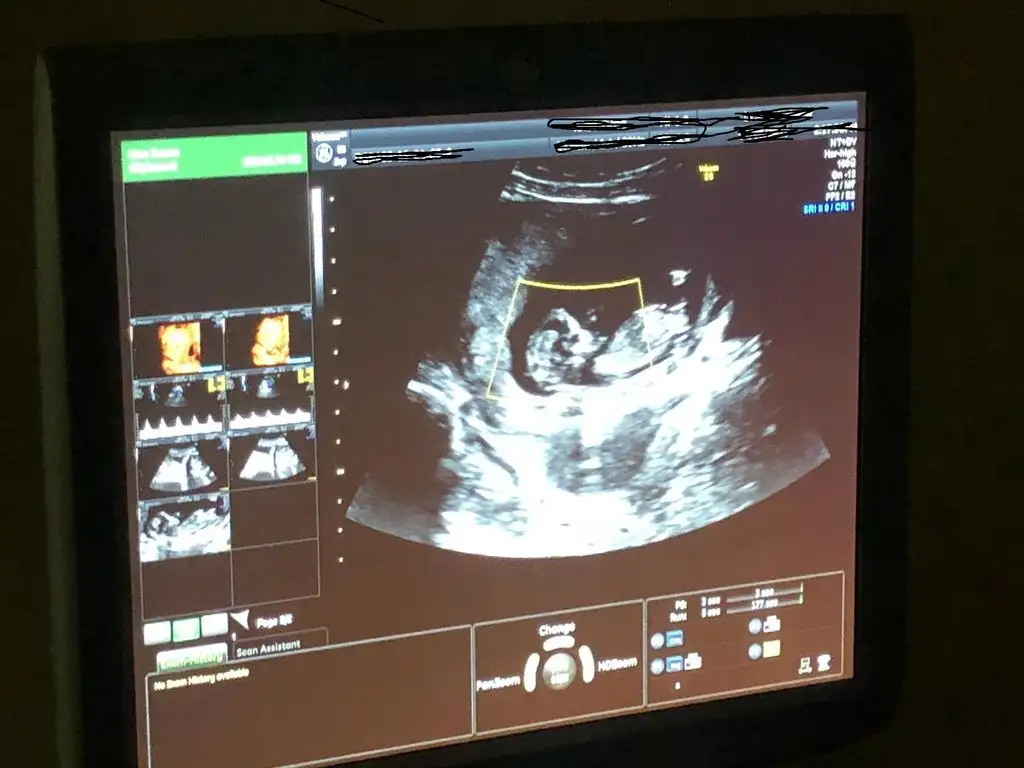

banada yorumda bulunurmusunuz ?? kızlar

kızlar banada yorumda bulunurmusunuz 15 gün sonra rndevum war ??

• WhatsApp Image 2019-04-03 at 17.19.06.webp

WhatsApp Image 2019-04-03 at 17.19.06.webp

35,6 KB · Görüntüleme: 73

13 haftalık olduk canm suan resim 11 haftalığa ait :) bir kızım war bunuda erkek istiyoduk Allah hayırlısını versin inşllah =)